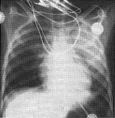

El edema pulmonar agudo ha sido explicado durante los últimos 20 años como el resultado de un aumento de la permeabilidad vascular pulmonar ocasionada por la acción de sustancias vasoactivas liberadas por el veneno y/o por la hipertensión arterial aguda de naturaleza adrenérgica que puede inducir fal la ventricular izquierda. Pero en los últimos 4 años se han publicado casos clínicos de pacientes que han desarrollado edema agudo de pulmón sin haber tenido complicaciones cardiacas. Lo que ha llevado a pensar que existe otro mecanismo de acción del anteriormente propuesto. En los últimos años investigadores\Brasileños y Venezolanos han demostrado que el edema pulmonar por escorpionismo ocurre por una vía indirecta. Este edema puede ser prevenido con heparina en animales experimentales. Investigaciones recientes realizadas en Venezuela (D 'Suze et al 1998, Toxicon) han sugerido la presencia de un síndrome de dificultad respiratoria por escorpionismo, el cual puede ser prevenido con heparina ya que envuelve a la cascada de coagulación sanguínea.

EDEMA AGUDO DE PULMON POR ESCORPIONISMO ¿UNA NUEVA ENTIDAD CLINICA?.